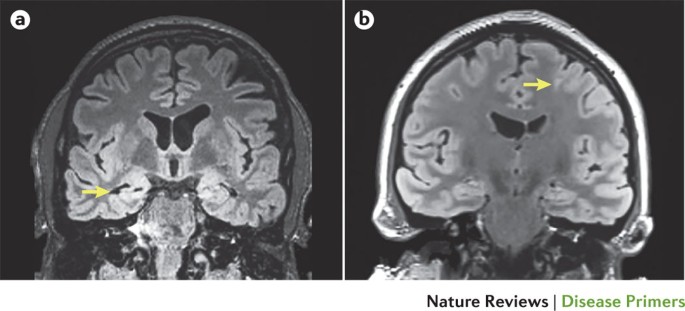

Epilepsy Nature Reviews Disease Primers

Frontiers Current And Emerging Potential Of

Structural Magnetic Resonance Imaging In Epilepsy Springerlink

Children Free Full Text Morphological And Advanced

Predicting The Response To Therapeutic Interventions Part